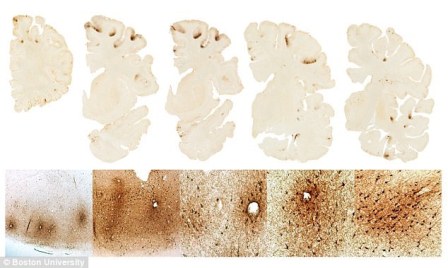

Các lớp cắt mô não. (Nguồn: dailymail.co.uk)

Nghiên cứu này đã phát hiện được sự gia tăng mật độ protein CCLL11 trong não bộ của những cầu thủ bóng đá bị mắc CTE đã chết, nhưng không tìm thấy nó ở trong não bộ của những người khỏe mạnh hoặc người bị bệnh Alzheimer.